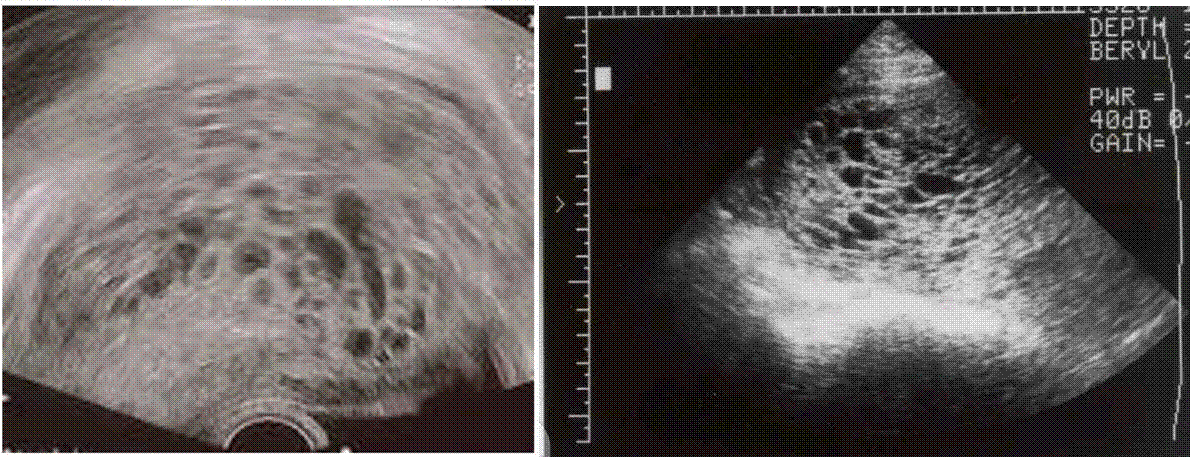

PHM USS FINDINGS

• Ultrasound

• Snowstorm appearance

• In partial mole: focal trophoblastic changes and fetal tissue may be noted

• Theca lutein cyst may be seen